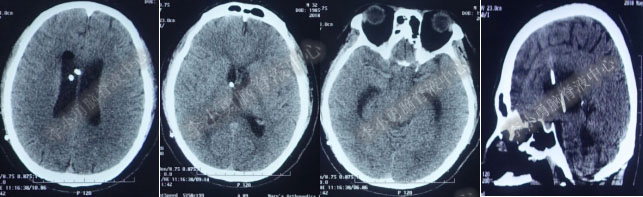

2017年6月19日(第1次内镜术后404天即一年零39天),因原症状加重,第2次住入该院。2017年6月20日(住院第2天),复查头部MRI(图-5)。

图-5:2017年6月20日头部MRI

2017年6月27日(分流术后5天),复查头部CT(图-6)显示幕上脑室及第四脑室均有所缩小。

图-6:2017年6月27日头部CT

图-7:2017年7月30日头部CT

图-8:2017年9月18日头部CT

图-9:2017年10月15日头部CT

第4次出院后11天即2018年4月15日(分流术后284天,第2次的软性内镜术后179天),因引流管堵塞第5次住入该院,引流管内白色絮状物增多,引流管被堵塞。入院当天复查头部CT(图-10)显示脑室系统仍扩张。

图-10:2018年4月15日头部CT

第5次入院第2天即2018年4月17日,脑室腹壁外引流管堵塞,意识恶化,复查头部CT(图-11)示全脑室系统又较前扩大。当天急诊行左侧脑室穿刺外引流术。脑脊液化验外观黄色浑浊,并且送培养,结果是无菌生长。

图-11:2018年4月17日头部CT脑室扩张又加重

第5次入院第3天即2018年4月18日术后复查头部CT(图-12)显示脑室系统扩张较前好转。

图-12:2018年4月18日头部CT